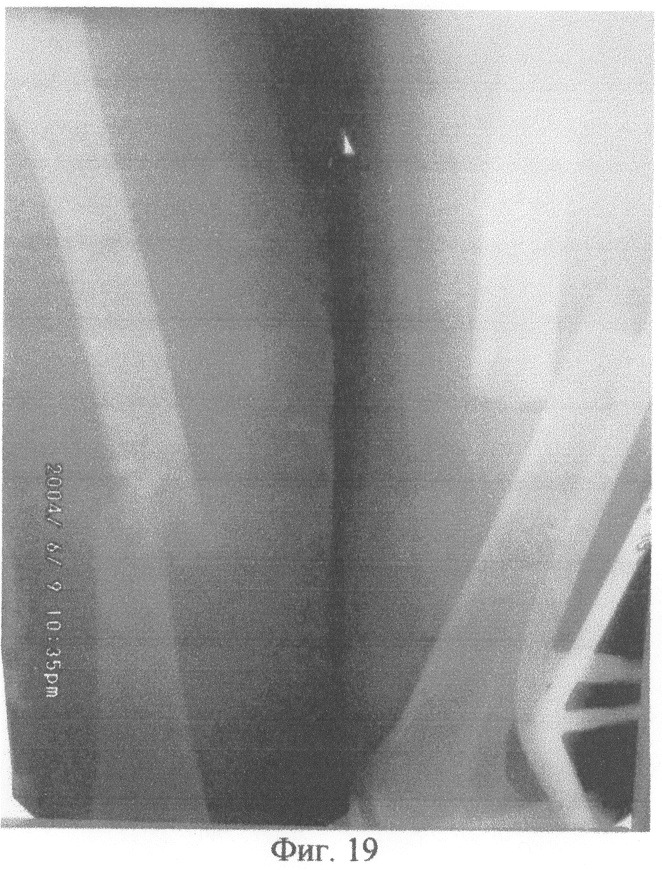

На фиг.1 изображено определение длины канюлированного стержня по отметке на шкале направляющей спицы. На фиг.2 – приведение в соответствие отверстий в блоке дистального целенаправителя отверстиям на рабочем конце канюлированного стержня с помощью контрольного инструмента. На фиг.3 – введение подготовленного канюлированного стержня по направляющей спице в костно-мозговой канал. На фиг.4 – выдвижение держателем направляющей спицы. На фиг.5 – контроль прохождения сверла через ниже расположенное отверстие на рабочем конце канюлированного стержня с помощью направляющей спицы и по отметке на шкале направляющей спицы. На фиг.6 – контроль прохождения блокирующего винта через ниже расположенное отверстие на рабочем конце канюлированного стержня с помощью направляющей спицы и по отметке на шкале направляющей спицы. На фиг.7 – контроль прохождения сверла через выше расположенное отверстие на рабочем конце канюлированного стержня и по отметке на шкале направляющей спицы. На фиг.8 – контроль прохождения блокирующего винта через выше расположенное отверстие на рабочем конце канюлированного стержня с помощью направляющей спицы и по отметке на шкале направляющей спицы. На фиг.9 – прохождение сверла впереди канюлированного стержня и проведение контроля отсутствия сверла в ниже расположенном отверстии на рабочем конце канюлированного стержня с помощью направляющей спицы и по отметке на шкале направляющей спицы. На фиг.10 – прохождение сверла позади канюлированного стержня и проведение контроля отсутствия сверла в ниже расположенном отверстии на рабочем конце канюлированного стержня с помощью направляющей спицы и по отметке на шкале направляющей спицы. На фиг.11 – сопротивление сверлу канюлированным стержнем и проведение контроля отсутствия сверла в ниже расположенном отверстии на рабочем конце канюлированного стержня с помощью направляющей спицы и по отметке на шкале направляющей спицы. На фиг.12 – определение спицей Киршнера ниже расположенного отверстия на рабочем конце канюлированного стержня и проведение контроля положения спицы Киршнера в ниже расположенном отверстии на рабочем конце канюлированного стержня с помощью направляющей спицы и по отметке на шкале направляющей спицы. На фиг.13 – контроль прохождения сверла через ниже расположенное отверстие на рабочем конце канюлированного стержня с помощью направляющей спицы и по отметке на шкале направляющей спицы. На фиг.14 – контроль прохождения блокирующего винта через ниже расположенное отверстие на рабочем конце канюлированного стержня с помощью направляющей спицы и по отметке на шкале направляющей спицы. На фиг.15 – сопротивление сверлу канюлированным стержнем и проведение контроля отсутствия сверла в выше расположенном отверстии на рабочем конце канюлированного стержня с помощью направляющей спицы и по отметке на шкале направляющей спицы. На фиг.16 – определение спицей Киршнера выше расположенного отверстия на рабочем конце канюлированного стержня и проведение контроля положения спицы Киршнера в выше расположенном отверстии на рабочем конце канюлированного стержня с помощью направляющей спицы и по отметке на шкале направляющей спицы. На фиг.17 – контроль прохождения сверла через выше расположенное отверстие на рабочем конце канюлированного стержня с помощью направляющей спицы и по отметке на шкале направляющей спицы. На фиг.18 – контроль прохождения блокирующего винта через выше расположенное отверстие на рабочем конце канюлированного стержня с помощью направляющей спицы и по отметке на шкале направляющей спицы. На фиг.19 – рентгенограмма левой бедренной кости в двух проекциях больного Квашнина Д.В. до операции. На фиг.20 – рентгенограмма левой бедренной кости в двух проекциях больного Квашнина Д.В. после операции. На фиг.21 – рентгенограмма костей левой голени в двух проекциях больной Корхалевой Е.Н. до операции. На фиг.22 – рентгенограмма костей левой голени в двух проекциях больной Корхалевой Е.Н. после операции.

Под интубационным наркозом на ортопедическом столе произведена закрытая репозиция отломков левой бедренной кости, в костно-мозговой канал введена направляющая спица. Произведена контрольная рентгенограмма левой бедренной кости в двух проекциях передвижным рентгенаппаратом. По отметке на шкале направляющей спицы определена длина канюлированного стержня (460 мм). Произведена подготовка дистального целенаправителя: приведены в соответствие отверстия в блоке дистального целенаправителя отверстиям на рабочем конце канюлированного стержня с помощью контрольного инструмента. Введен в костно-мозговой канал по направляющей спице подготовленный канюлированный стержень длиной 460 мм. Держателем выдвинута направляющая спица. Через нижнее отверстие в блоке дистального целенаправителя сверлом сформирован канал в близлежащем кортикальном слое кости. Продолжая сверление, сверло не проходило в ниже расположенное отверстие на рабочем конце канюлированного стержня вследствие деформации рабочего конца канюлированного стержня во время введения его в костно-мозговой канал. Отсутствие сверла в ниже расположенном отверстии рабочего конца канюлированного стержня контролировали следующим образом: держателем направляющая спица проведена по каналу стержня в дистальном направлении, она не встретила сопротивления сверла на уровне ниже расположенного отверстия на рабочем конце канюлированного стрежня, прошла дистальнее; по отметке на шкале направляющей спицы показатель равен 460 мм, то есть больше разницы между длиной канюлированного стержня (460 мм) и расстоянием от рабочего конца канюлированного стержня до уровня ниже расположенного отверстия на рабочем конце канюлированного стержня (20 мм). Удалено сверло, снят дистальный целенаправитель. В отверстие в близлежащем кортикальном слое кости введена спица Киршнера, которой определено ниже расположенное отверстие на рабочем конце канюлированного стержня. Контроль положения спицы Киршнера в ниже расположенном отверстии на рабочем конце канюлированного стержня осуществлен следующим образом: держателем направляющая спица проведена в дистальном направлении по каналу стержня, она встретила сопротивление спицы Киршнера на уровне ниже расположенного отверстия на рабочем конце канюлированного стержня; по отметке на шкале направляющей спицы показатель равен 440 мм, что соответствует разнице между длиной канюлированного стержня (460 мм) и расстоянием от рабочего конца канюлированного стержня до уровня ниже расположенного отверстия на рабочем конце канюлированного стержня (20 мм). Сверлом соответственно направлению спицы Киршнера сформирован канал в кости, проходящий через ниже расположенное отверстие на рабочем конце канюлированного стержня. Контроль прохождения сверла через ниже расположенное отверстие на рабочем конце канюлированного стержня осуществлен следующим образом: держателем направляющая спица проведена в дистальном направлении по каналу стержня, она встретила сопротивление сверла на уровне ниже расположенного отверстия на рабочем конце канюлированного стержня; по отметке на шкале направляющей спицы показатель равен 440 мм, что соответствует разнице между длиной канюлированного стержня (460 мм) и расстоянием от рабочего конца канюлированного стержня до уровня ниже расположенного отверстия на рабочем конце канюлированного стержня (20 мм). Просверлен второй кортикальный слой кости, удалено сверло. В сформированный канал введен блокирующий винт. Контроль прохождения блокирующего винта через ниже расположенное отверстие на рабочем конце канюлированного стержня осуществлен следующим образом: держателем направляющая спица проведена в дистальном направлении по каналу стержня, она встретила сопротивление блокирующего винта на уровне ниже расположенного отверстия на рабочем конце канюлированного стержня; по отметке на шкале направляющей спицы показатель равен 440 мм, что соответствует разнице между длиной канюлированного стержня (460 мм) и расстоянием от рабочего конца канюлированного стержня до уровня ниже расположенного отверстия на рабочем конце канюлированного стержня (20 мм). Установлен дистальный целенаправитель. Через верхнее отверстие в блоке дистального целенаправителя сверлом сформирован канал в близлежащем кортикальном слое кости, продолжая сверление, сверло прошло в выше расположенное отверстие на рабочем конце канюлированного стержня. Контроль прохождения сверла через выше расположенное отверстие на рабочем конце канюлированного стержня осуществлен следующим образом: держателем направляющая спица проведена в дистальном направлении по каналу стержня, она встретила сопротивление сверла на уровне выше расположенного отверстия на рабочем конце канюлированного стержня; по отметке на шкале направляющей спицы показатель равен 415 мм, что соответствует разнице между длиной канюлированного стержня (460 мм) и расстоянием от рабочего конца канюлированного стержня до уровня выше расположенного отверстия на рабочем конце канюлированного стержня (45 мм). Просверлен второй кортикальный слой кости, удалено сверло. Через верхнее отверстие в блоке дистального целенаправителя введен в сформированный канал блокирующий винт. Контроль прохождения блокирующего винта через выше расположенное отверстие на рабочем конце канюлированного стержня осуществлен следующим образом: держателем направляющая спица проведена в дистальном направлении по каналу стержня, она встретила сопротивление блокирующего винта на уровне выше расположенного отверстия на рабочем конце канюлированного стержня; по отметке на шкале направляющей спицы показатель равен 415 мм, что соответствует разнице между длиной канюлированного стержня (460 мм) и расстоянием от рабочего конца канюлированного стержня до уровня выше расположенного отверстия на рабочем конце канюлированного стержня (45 мм). Произведено проксимальное блокирование канюлированного стержня. Сделана рентгенограмма в двух проекциях передвижным рентгенаппаратом (фиг.20). Продолжительность операции 1 час.